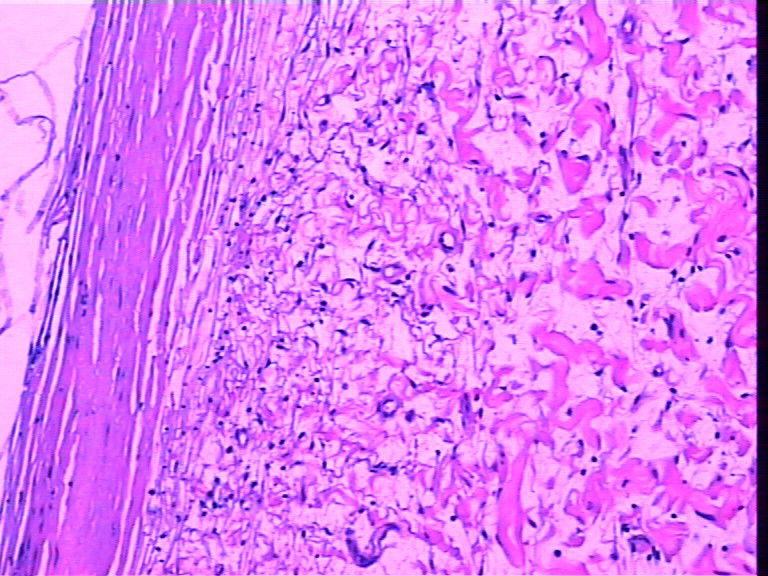

腹壁一个包块,大小4cmx2cmx2cm,椭圆形,有菲薄包膜,淡黄色,切面淡黄色半透明,质地偏韧。

腹壁一个包块,巨检长相很似神经鞘瘤,不知是什么东东图1

腹壁一个包块,巨检长相很似神经鞘瘤,不知是什么东东图2

名称:图1

腹壁一个包块,巨检长相很似神经鞘瘤,不知是什么东东图3

名称:图2

腹壁一个包块,巨检长相很似神经鞘瘤,不知是什么东东图4

名称:图3

描述:3

腹壁一个包块,巨检长相很似神经鞘瘤,不知是什么东东图5

名称:图4

描述:4

腹壁一个包块,巨检长相很似神经鞘瘤,不知是什么东东图6

名称:图5

描述:5

腹壁一个包块,巨检长相很似神经鞘瘤,不知是什么东东图7

名称:图6

描述:6